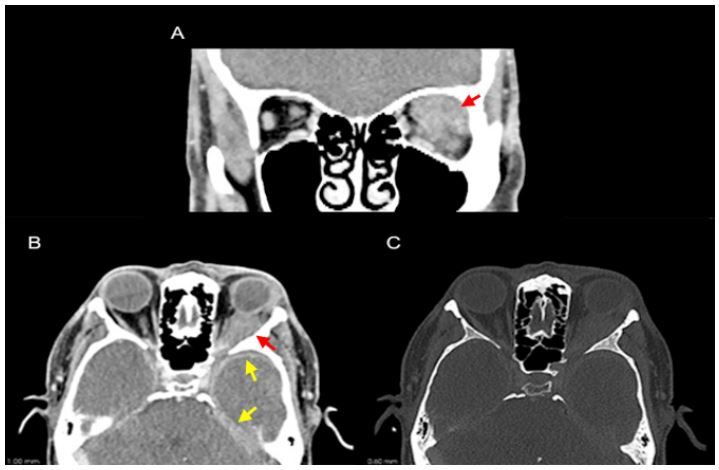

A 58-year-old man with a medical history of hypertension, controlled with candesartan and hydrochlorothiazide, and surgical history of left eye cataract surgery using retrobulbar anesthesia 1 month prior presented with complaints of blurry vision and headaches since the surgery. Ophthalmologic examination revealed left proptosis, chemosis and limitation of upwards and downwards eye gaze, without diplopia. A central scotoma and hyporeactive left pupil were also documented without clear relative afferent pupillary defect. Routine laboratory results were unremarkable. Urinalysis did not show proteinuria or hematuria. Computer Tomography (CT) (Figure 1) and Magnetic Resonance Imaging (MRI) (Figure 2) were performed that revealed a left intraorbital infiltrating soft tissue lesion with involvement of the superior and lateral rectus muscles and extension into the preseptal space, involving and enlarging the lacrimal gland. The lesion displaced the left optic nerve medially and the globe inferiorly. A right infiltrating orbital apex lesion with similar imaging characteristics was also documented. Intracranially, temporal and tentorial pachymeningeal thickening was also noted.

Figure 1: CT scan demonstrating a soft tissue density mass in the left orbit infiltrating the post-septal intra and extra-conal spaces in the left superior quadrant (A and B; red arrow) with antero-lateral extension to the left lacrimal gland and posterior extension to the cavernous sinus. Intracranially, bilateral left predominant temporal and tentorial pachymeningeal can also be noted (B; yellow arrow). No bony destruction was documented (C).